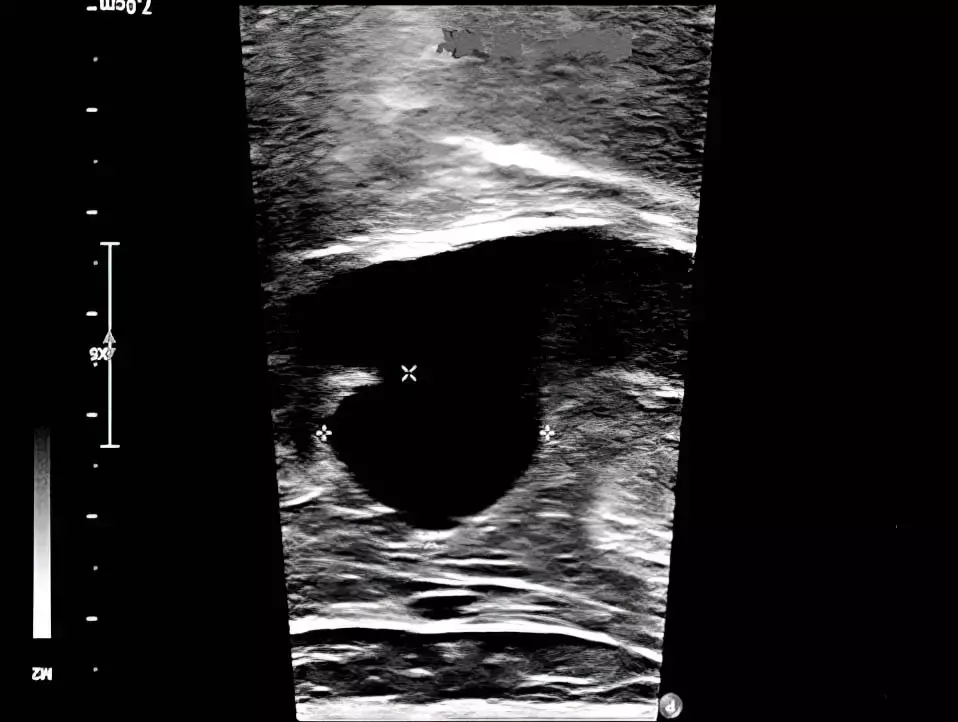

paiicyifc5Рисунок 3. Аневризма подколенной вены диаметром 32×42 мм на УЗИ.По данным УЗИ выявлена аневризма проксимальной части подколенной вены диаметром 32×42 мм, с турбулентным кровотоком в полости аневризмы и эффектом спонтанного контрастирования (см. рис. 3).